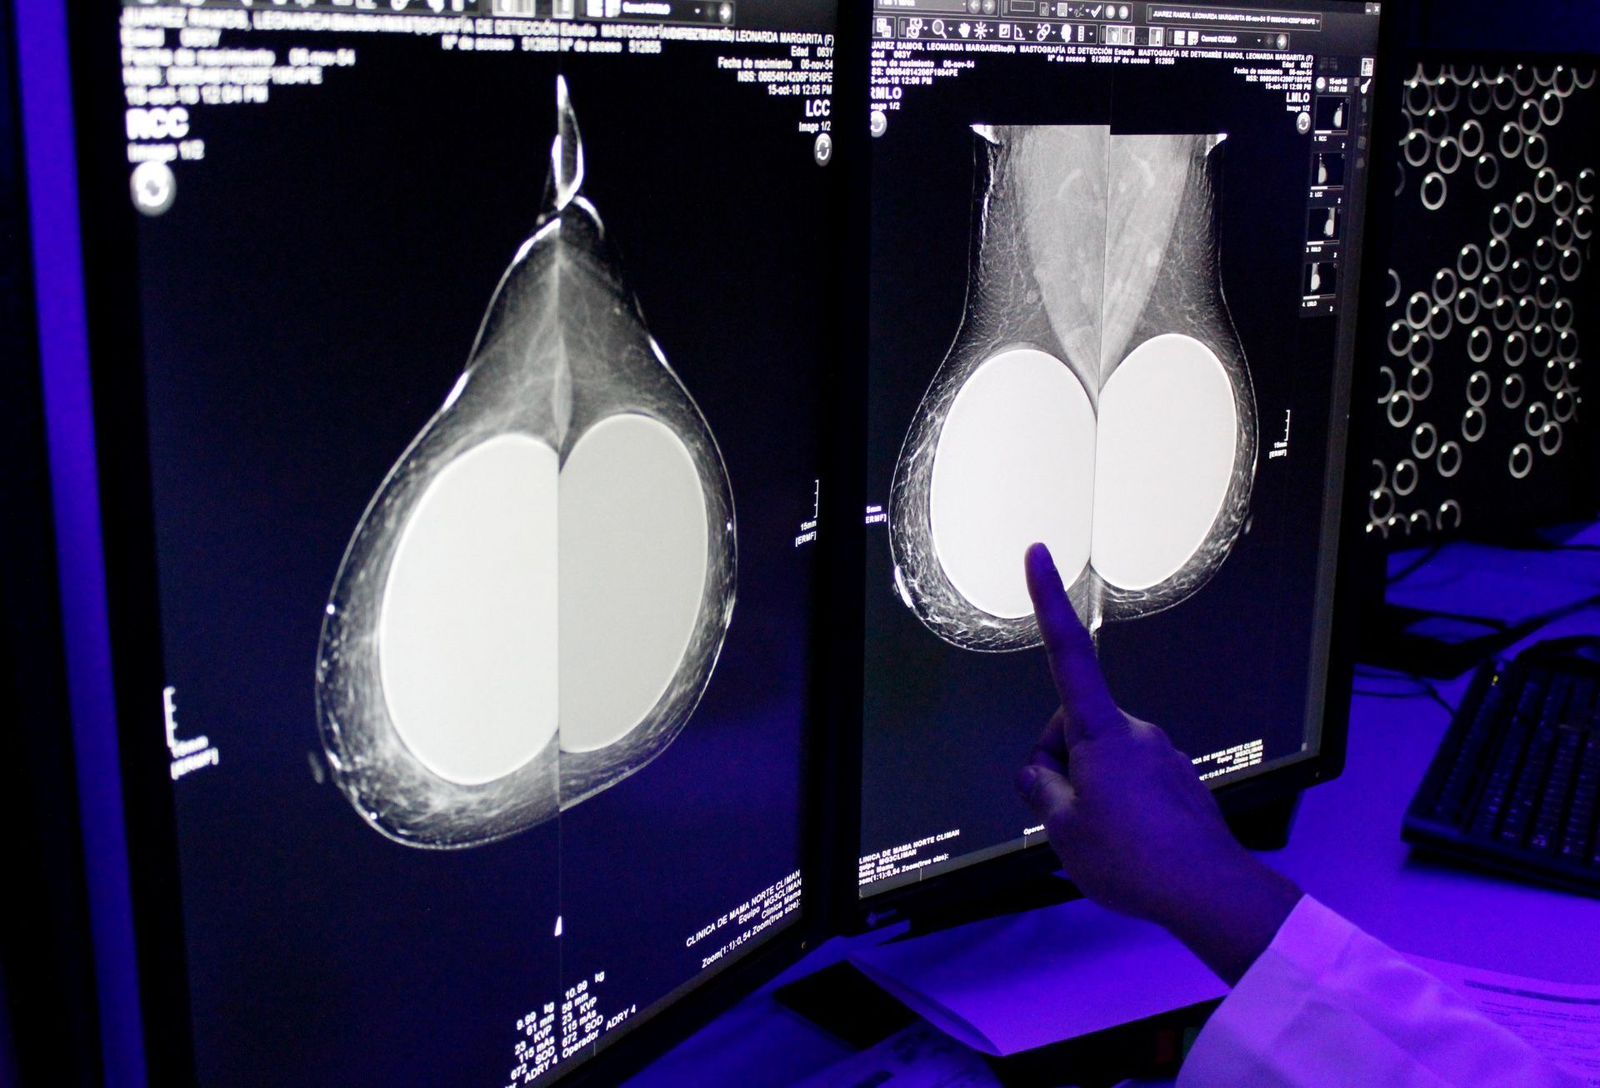

Explicó que actualmente hay sólo 656 mastógrafos operando en el sistema público, por lo que el Gobierno adquirirá mil mastógrafos y mil ultrasonidos adicionales entre 2026 y 2027.

Además se establecerán 20 centros de diagnóstico a distancia, que se sumarán a los 64 ya existentes. Así la radiografía y el ultrasonido, se podrán enviar digitalmente y especialistas interpretarán, para dar un diagnóstico más eficaz.